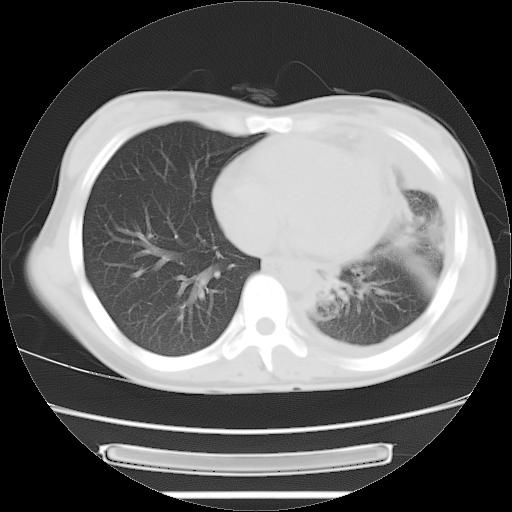

标题: CT21561:外院胸片提示胸腔积液,行CT检查。 [打印本页]

女,29岁,胸部不适,在外院胸片提示胸腔积液,到我院ct检查。

肺窗:

左肺上叶不张,左侧胸水,叶间裂积液,纵隔淋巴结,脾脏钙化,考虑左肺上叶支气管内膜结核,结核性胸膜炎,脾结核